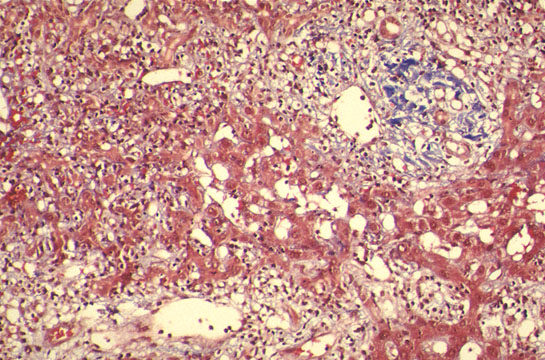

Fig 111 - Marked Inflammation of all portal fields. Notice three portal fields infiltrated by inflammatory cells with erosion of limiting plates. Score=4

Interface hepatitis

Fig 112 - Interface hepatitis: Marked mononuclear

infiltration of all portal tracts with erosion of limiting

plates and piecemeal necrosis. Score=4

Lobular inflammation

Fig 113 - Lobular inflammation: There is no confluent

necrosis but there is focal necrosis with Councilman bodies,

one with a pyknotic nucleus. Score=2

Fibrous changes

Fig 114 - Fibrous changes: Fibrous expansion of all portal

fields with occasional portal-portal Bridging. Score=3